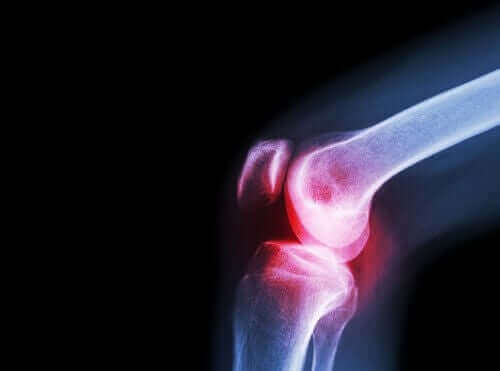

Лікарі призначають цей препарат у випадках, коли пацієнт потребує лікування запальних і хворобливих станів, таких як біль у попереку, зубний біль та біль у суглобах.

Також лікарі призначають його для лікування хронічного болю та запалення, пов’язаних з хронічними суглобовими процесами: остеоартритом, ревматоїдним артритом та спондилітом.

З точки зору симптомів, ревматоїдний артрит, як правило, проявляється болем і скутістю, а також утрудненням пересування різних малих і великих суглобів.

Лікарі рекомендують ацеклофенак і при цьому розладі. Остеоартрит – ще одне ревматичне захворювання, яке пошкоджує хрящі суглобів.

Коли цей хрящ пошкоджений, виникають біль, скутість та функціональна інвалідність. Тому важливо відрізняти це захворювання від артриту. Останній розвивається через запалення суглобів, а не знос хрящів.